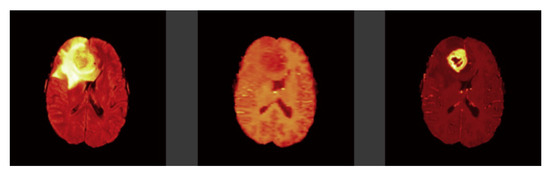

Figure 3.

Dataset Samples from BraTS-2019.

3. Dataset for Brain Cancer

The MICCAI BraTS training dataset from 2019 is used to train the segmentation model. It is composed of 335 patients and 4 distinct modalities (T1, T2, T1CE, and Flair). Some sample images are shown in Figure 3. NIfTI scans [78] have been obtained using a variety of clinical procedures, as well as a variety of scanners from 19 different institutions. All images were manually segmented by one to four raters, following the same annotation methodology, and the annotations were approved by expert neuroradiologists. Annotations’ labels concern the enhancing tumor (label 4), the peritumoral edema (label 2), the necrotic and non-enhancing tumor core (label 1), and everything else in the picture (label 0). Pre-processing included co-registration to the same anatomical template, interpolation to the same resolution (1 mm3), and skull-stripping [79,80,81]. Each patient is made up of 155 images termed slices of each modality. The data collection includes both low-grade glioma (LGG) and high-grade glioma (HGG) cases, with tumor classifications determined by specialists in the field. There are 76 LGG patients and 259 HGG patients in the data collection, for a total of 335 individuals.